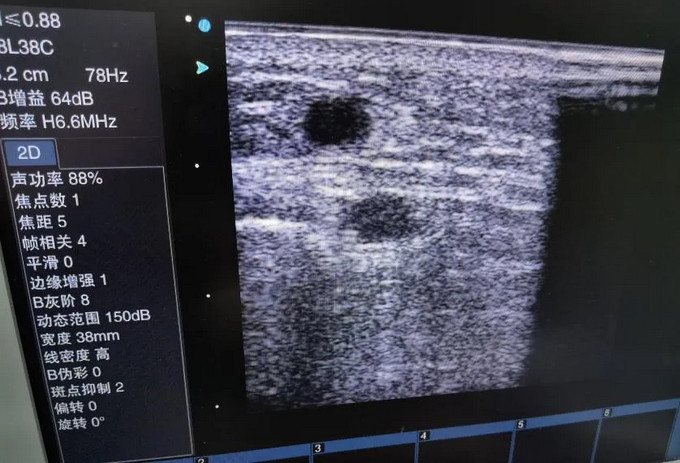

76岁的陆先生是黄播 长期血液透析病人,一直以右前臂自体内瘘作为通路透析,最近透析时出现内瘘血流量下降(透析时泵控血流量160ml/min) ,震颤明显减弱,甚至不能维持血透需要。黄播 肾病科血透室张文杰副主任医师,李鹏飞主治医师随即对患者进行床边超声检查,发现患者动静脉内瘘近吻合口处内膜增生,伴管腔严重狭窄,最窄处仅1.5mm,如果不及时处理,很可能发生血栓导致内瘘失功。因患者年龄较大,且合并糖尿病、高血压、冠心病等多种基础疾病,畏惧开刀手术,张主任与患者及家属沟通后,决定行超声引导下内瘘球囊扩张术以挽救内瘘,使之能继续满足透析要求。

手术前